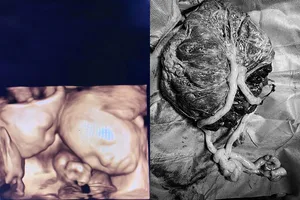

Cứu sống thai nhi “chui” ra ổ bụng do sản phụ vỡ tử cung

Cứu sống mẹ và con của sản phụ nguy kịch vì bị nhau cài răng lược

Lần đầu tiên mổ thành công ca song thai hiếm gặp